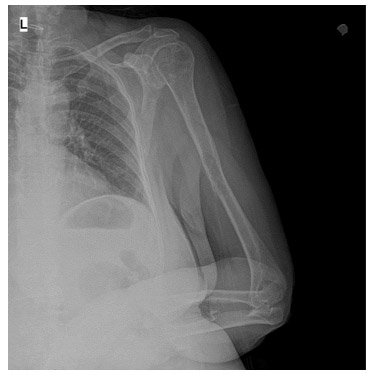

CASE 5: Fracture due to breast cancer metastasis to the left arm (humerus) bone.

Before the surgery: A displaced and undisplaced fracture is observed in the mid-region of the left arm (humerus).